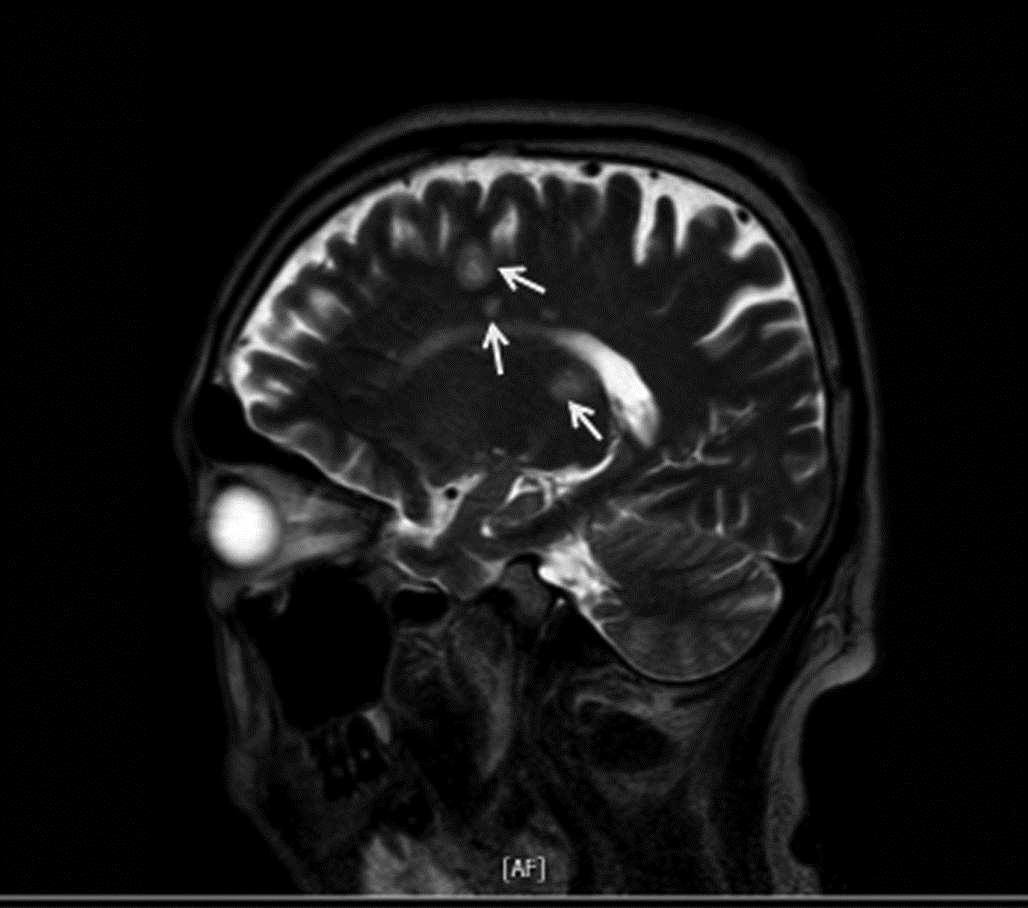

Brain abscess secondary to liver abscess in type 2 diabetes mellitus: A case report

Deyun WANG, Ruirui JIN, Zhen ZHAO, Hui LI

2022, 38(6): 1375-1376. DOI: 10.3969/j.issn.1001-5256.2022.06.031

Abstract(963) HTML (281) PDF (1890KB)(70)

Abstract: